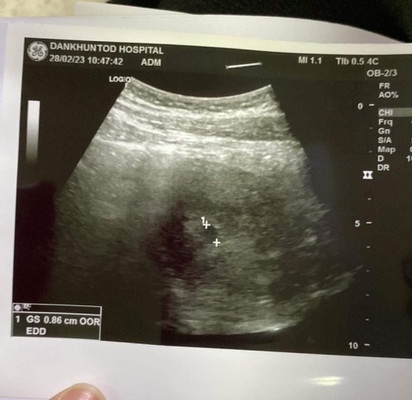

ใครเคยฝากท้องแล้วหมอซาวด์เจอแต่ถุงตั้งครรภ์บ้างคะ ถ้าคำนวนจากปจด.มาล่าสุด19ม.ค.66 อายุครรภ์ประมาณ5w5d แต่หมอซาวด์แล้วเจอแต่ถุงและบอกเราว่ายังคำนวณอายุครรภ์ไม่ได้นี่คืออะไรคะ ไม่ค่อยสบายใจเลยค่ะ#ขอคำแนะนำหน่อยค่ะ #ท้องแรกคะ